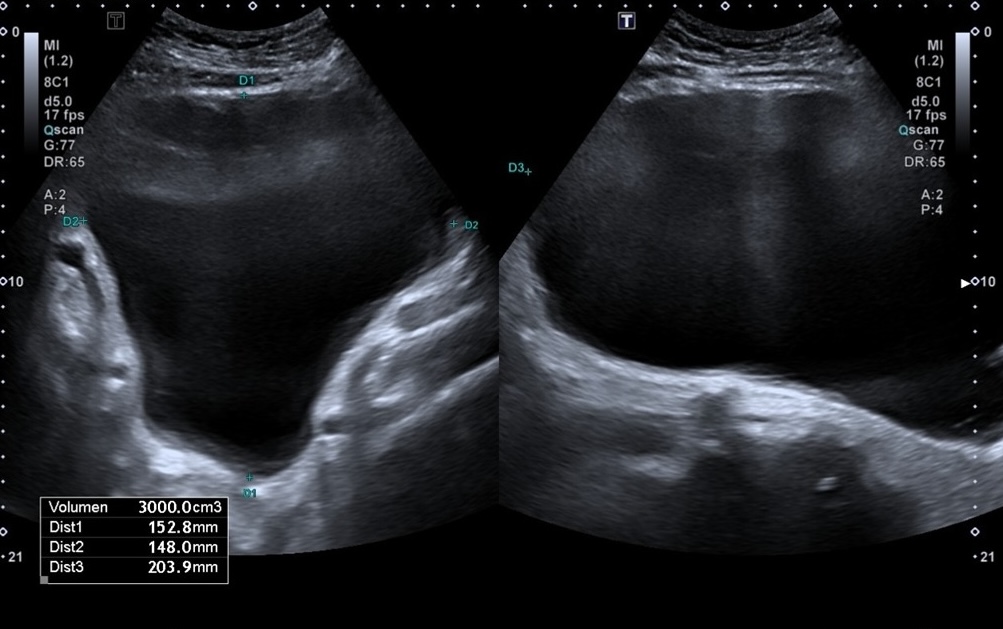

Ecografía abdominal: vejiga hiperdistendida con unos 3000 ml de orina y hidronefrosis bilateral moderada-severa, sin lesiones intravesicales ni causa obstructiva aparente. Analítica: anemia microcítica (Hb 9 g/dl), insuficiencia renal aguda grave (urea 409, creatinina 14,2), acidosis metabólica (pH 7,26; HCO₃ 6,3), PCR 19,7. Sedimento urinario positivo para infección.

Por el cuadro constitucional y vómitos, la primera sospecha fue neoplasia maligna. Sin embargo, la ecografía reveló retención urinaria masiva con afectación pielocalicial bilateral, orientando el diagnóstico hacia insuficiencia renal aguda obstructiva.

El paciente ingresa a cargo de urología. En la revaluación conjunta refiere clínica miccional crónica con empeoramiento reciente. Evolución favorable con mejoría clínica y analítica progresiva. Alta con diagnóstico de vejiga hipotónica, pendiente de tratamiento quirúrgico definitivo.